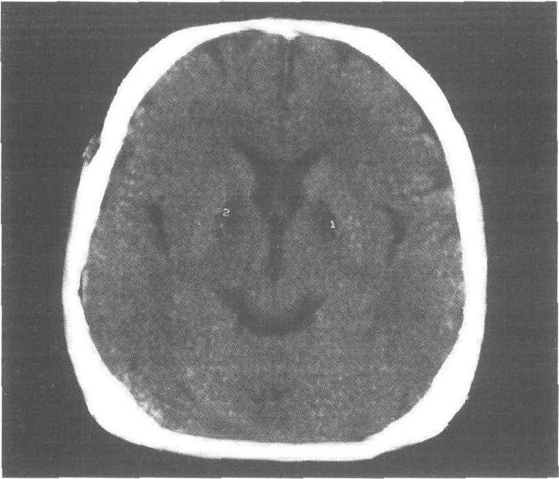

一氧化碳中毒(轻度急性期)CT平扫:双侧煞白球对称性低密度灶天元证券_线上实盘配资模式观察与交易行为解析报告,无脑水肿。